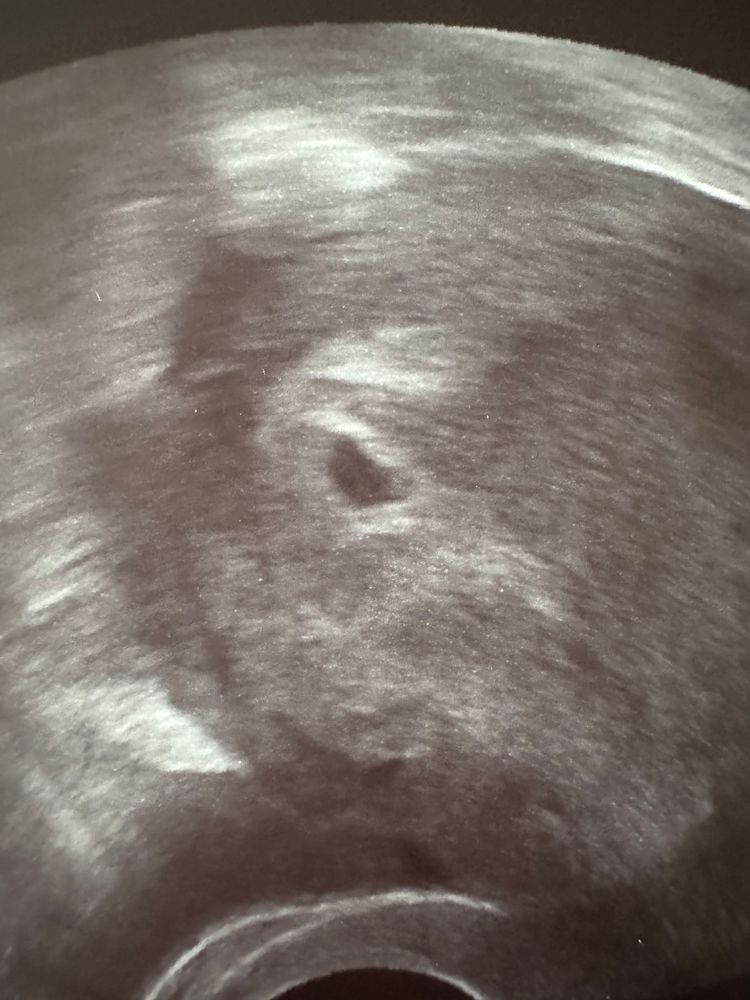

Ирина, вот так) Изображение

Евгения , мне кажется у вас тоже в уголочке сверху на втором фото что-то есть😊

Ирина, муж тоже говорит так)